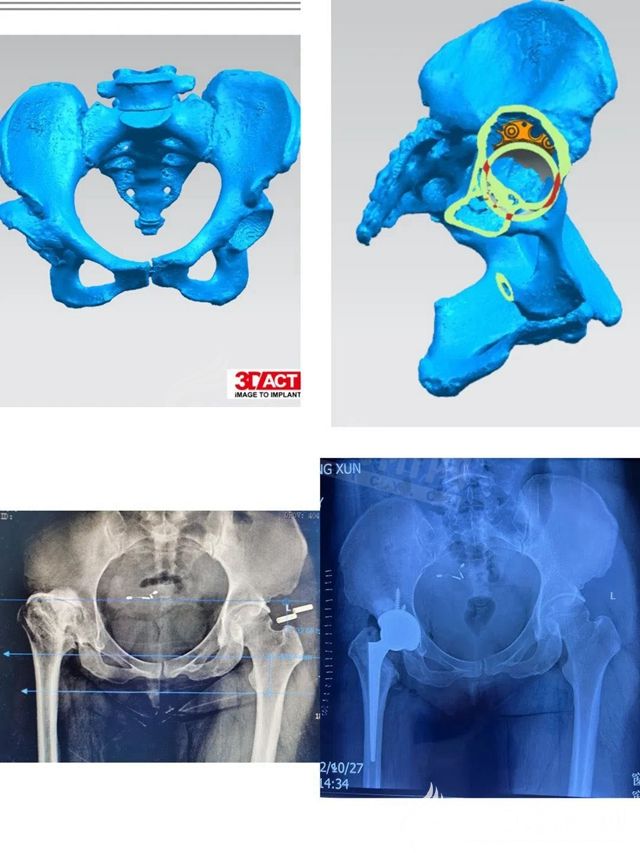

數(shù)字化骨科技術(shù)運用3D打印技術(shù)把患者的患病部位用多排CT術(shù)前掃描重建,然后根據(jù)數(shù)據(jù)用3D打印機打印出患者的病變部位,根據(jù)數(shù)字模型制作或準備與之匹配的關(guān)節(jié)假體和配套的手術(shù)器械,再進行手術(shù),以便減少手術(shù)創(chuàng)傷,使手術(shù)更加精準,手術(shù)質(zhì)量更有保障。而這個手術(shù)的難點就在于病人髖臼骨量缺損,股骨端畸形,周圍軟組織攣縮,術(shù)中還需要矯正雙下肢不等長,軟組織不平衡會導致術(shù)后脫位。

術(shù)前,趙新潔與骨傷一科主治醫(yī)生張愛東對患者進行了認真細致的檢查,組織科內(nèi)全體醫(yī)生進行會診討論,制定了嚴密的手術(shù)計劃。在麻醉科主任李鵬和醫(yī)生劉冬梅的協(xié)助下,手術(shù)近3個小時,矯正了雙下肢不等長,獲得成功。